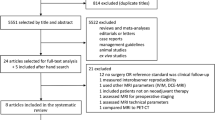

A total of 32 patients with newly diagnosed esophageal cancer were enrolled in the prospective study. Of these patients, 8 were excluded for the current analysis based on unexpected distant metastatic disease after nCRT (n = 2), tumor histology other than squamous cell carcinoma or adenocarcinoma as based on the primary tumor biopsy (n = 2), poor tumor visibility on DW-MRI (n = 3), or withdrawal from study participation (n = 1) (Supplementary Fig. 2). The final study population comprised 24 patients with a mean age of 65 years (± 8 years) and all but 2 were male (92%). The majority of the patients had an adenocarcinoma (67%). Median time between nCRT and esophagectomy was 10 weeks (IQR 7–14 weeks). A pCR (TRG 1) after nCRT was observed in 7 patients (29%). Table 1 gives an overview of the clinical characteristics of the study population.